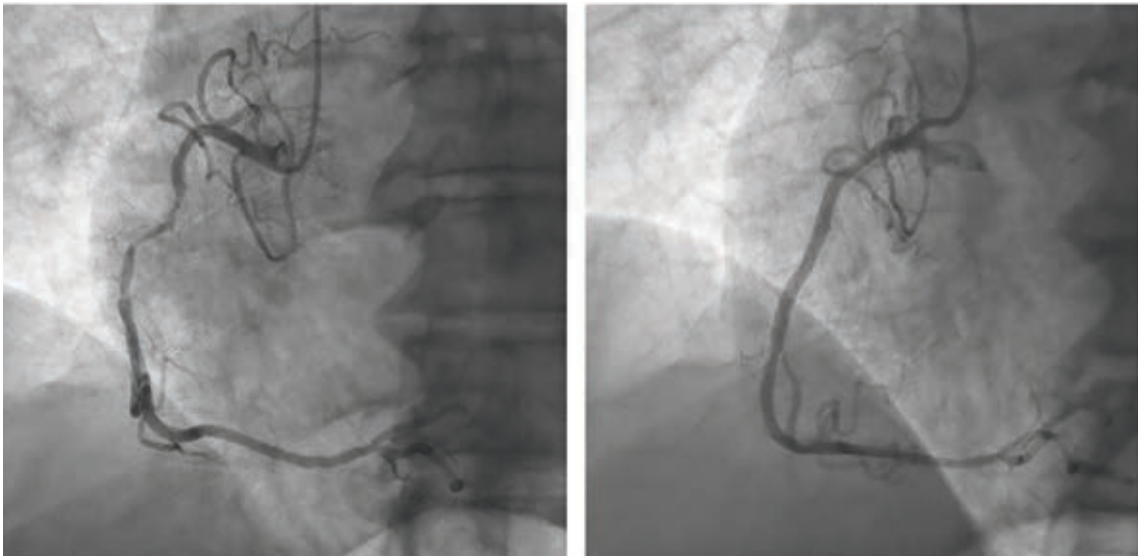

“Over the years as an interventionalist, writes Dr. Jeffrey Cook in Quincy, Illinois, “I have noticed a patient profile of an individual presenting somewhat late into their myocardial infarction (MI) — 12-24 hours or so — who seems to be overtly stable as they arrive at the emergency department (ED). Minimal pain, hemodynamics normal (or even hypertensive), oxygenation normal, no indication of decompensation noted. Everything seems perfectly routine. The patient is brought to the cath lab, the infarct-related artery is identified, wired, and ballooned — and from there, the patient decompensates. Even though the vessel has gone from 100% to 0%, suddenly the patient is hypotensive, with progressive respiratory distress, and progressing to shock. I have unfortunately been fooled by this presentation (Figures 1-4) many times, and I’m wondering a few things. First, what is the mechanism? Is it something to do with sudden washout of acidotic myocardium? Second, is there any way to predict that this is going to happen, and to take measures to prevent it? I recently had a patient present like this again, and I find myself extremely frustrated and distraught about it. Can you provide some guidance or direct me to appropriate literature? I’ve tried to find articles or even discuss it with other operators and have been stymied. I did find a thoughtful article by Yongbin Li et al,1 but it does not necessarily answer my questions.”